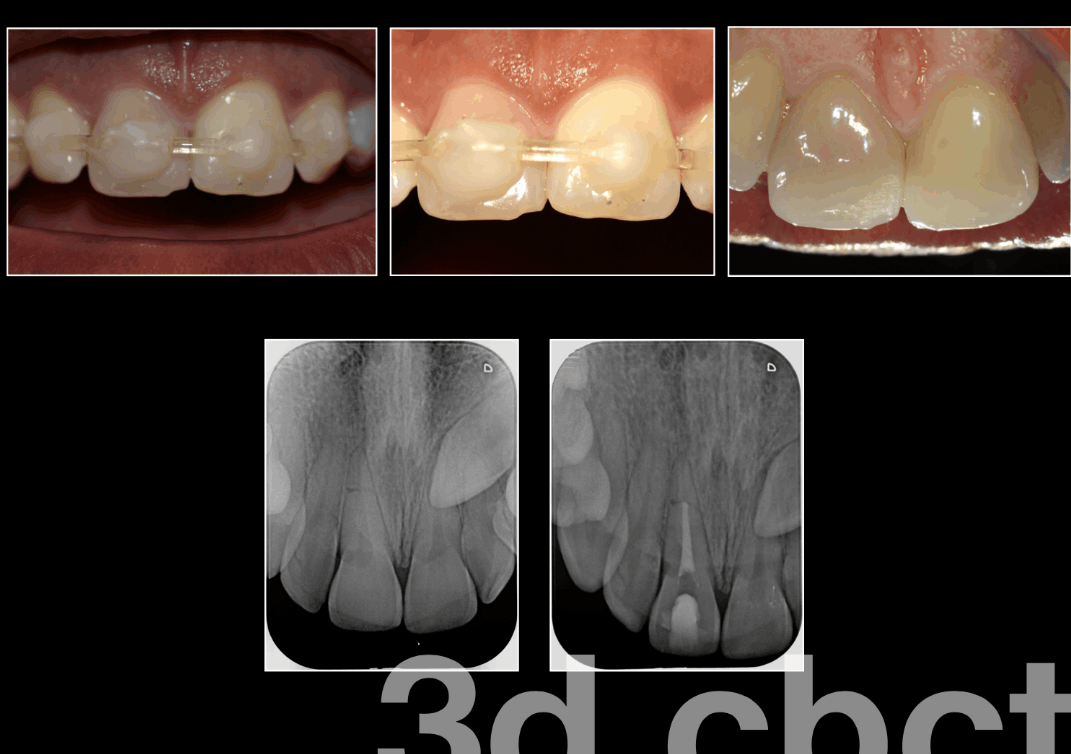

Diente fisurado tratable

Este tipo de fisura se extiende desde la superficie de masticación del diente y migra verticalmente hacia la raíz. En algunos casos, la grieta puede extenderse por debajo de la línea de las encías. Es posible que la grieta se extienda más hacia la raíz. El daño a la pulpa es común. En este caso, el tratamiento del conducto radicular suele ser necesario. Un diente roto que no se trata empeorará, lo que provocará la pérdida del diente. Por lo tanto, la detección temprana es esencial.